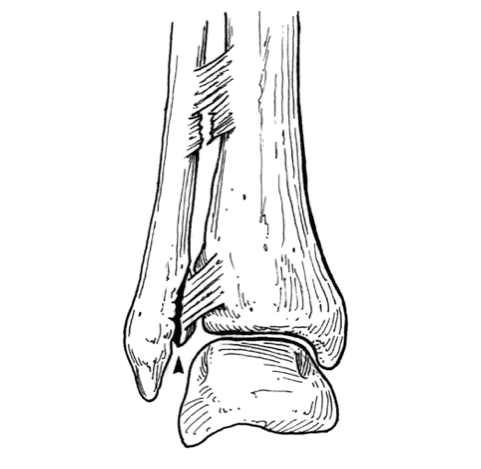

207

What is the more common side fractured in condylar fractures? Involvement of what section of bone makes a condylar fracture unstable?

- Lateral condyle more common - Involvement of the trochlear ridge makes it unstable - Surgical fixation if displaced >3mm Lateral, or >2mm Medial (A) Normal anatomy. (B) Lateral trochlear ridge not in fracture fragment (stable). (C) Lateral trochlear ridge included with fracture fragment (unstable).